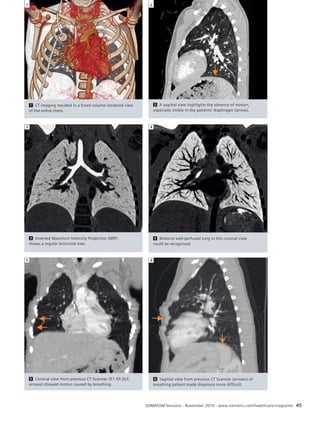

58 Differentiation of Pulmonary Emboli

and Their Effect on Lung Perfusion

Determined With a Low-Dose Dual

Energy Scan